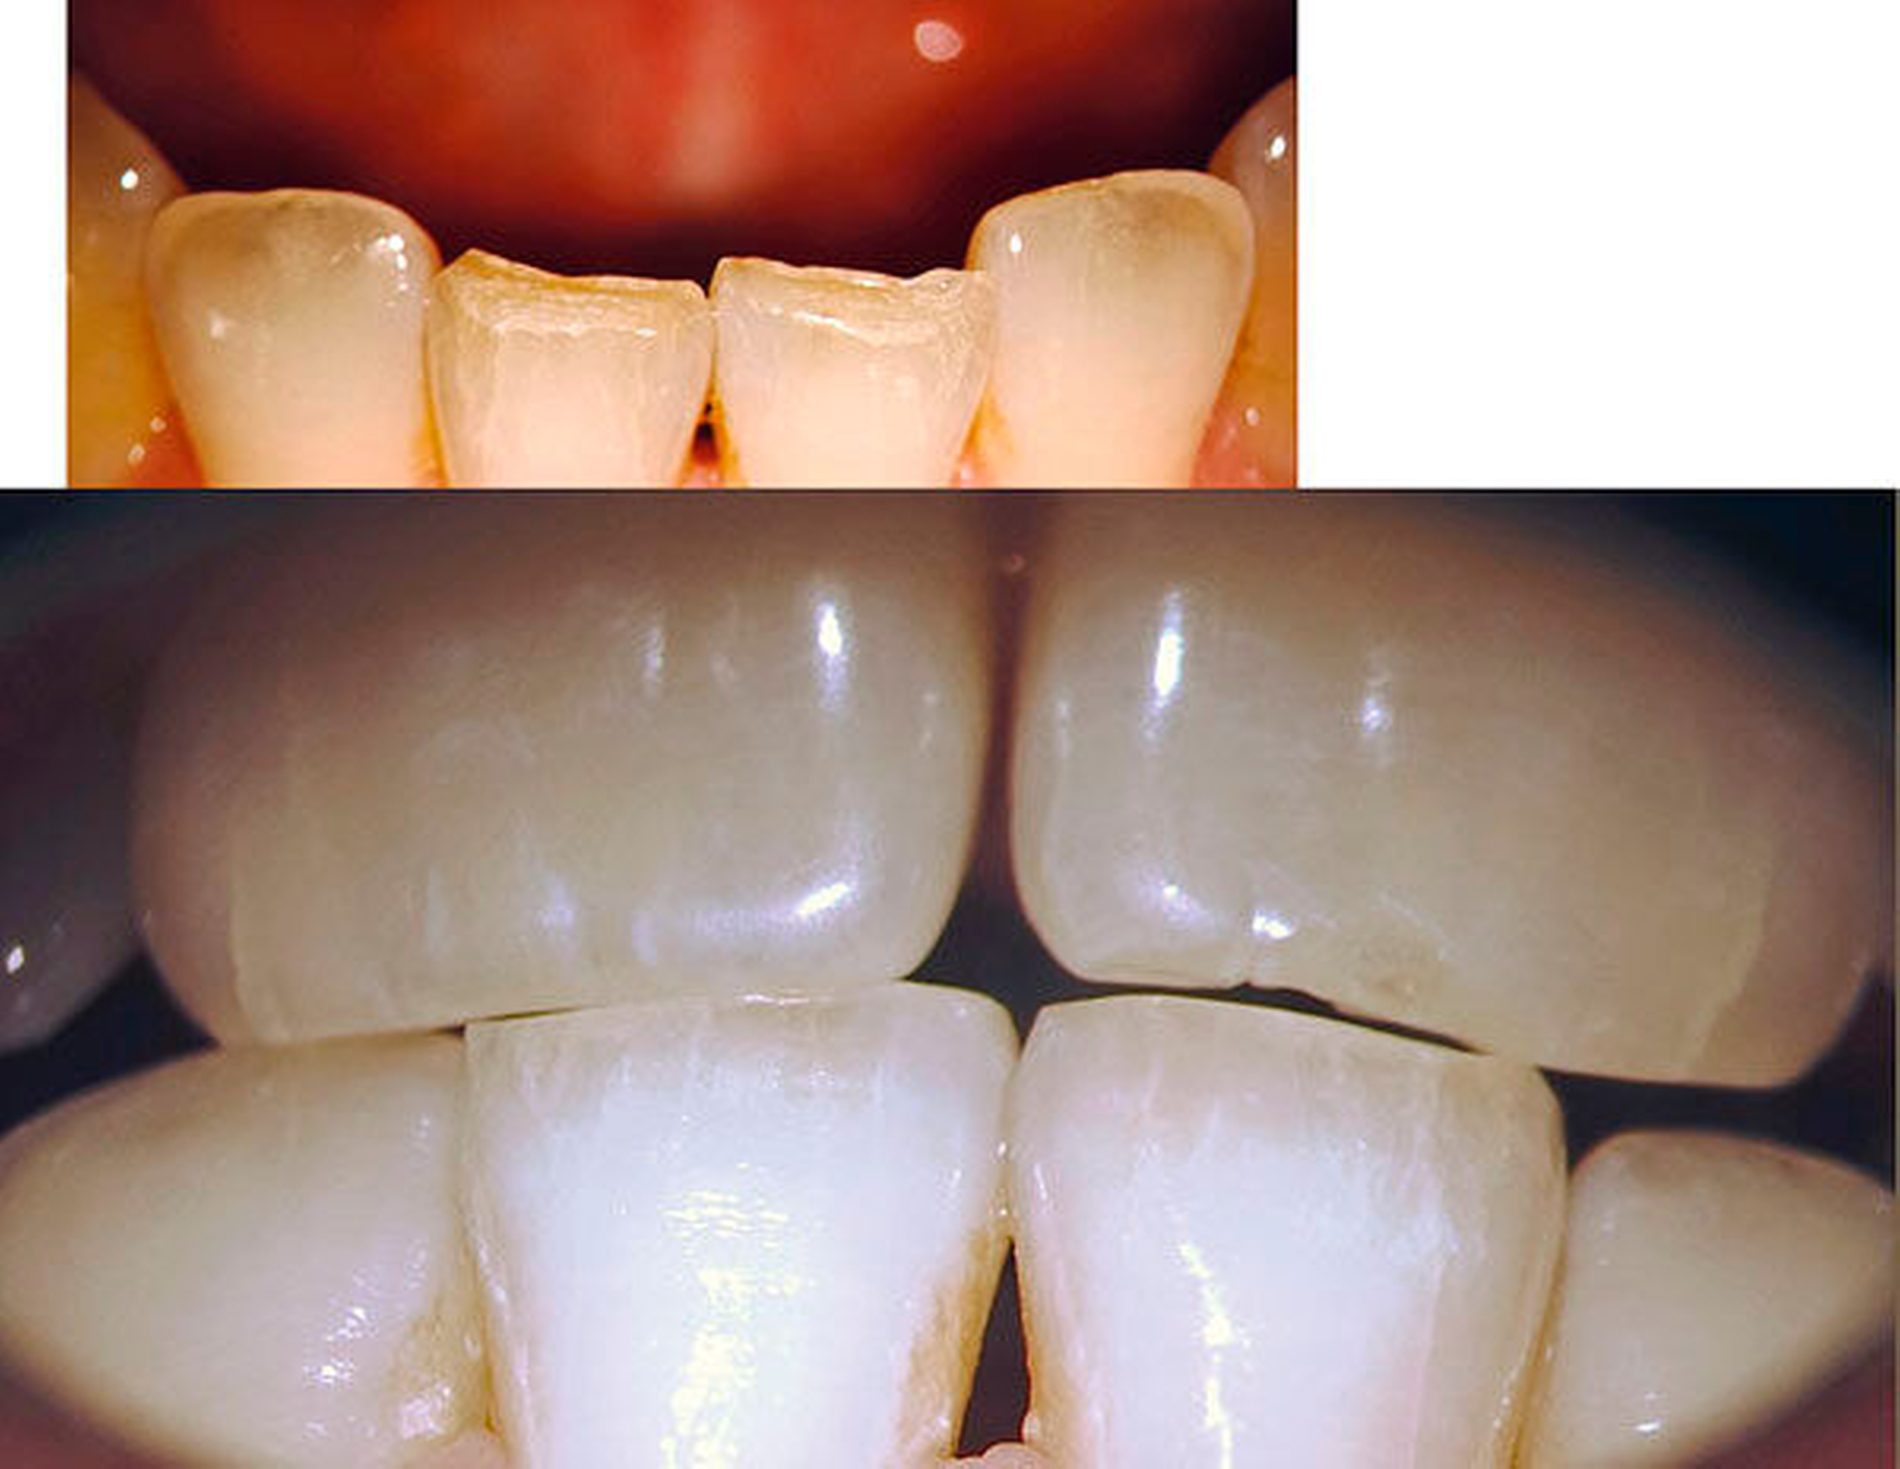

Im jugendlichen Gebiss zählen Zahnhartsubstanzverletzungen infolge eines akuten oder auch chronischen Zahnhartsubstanztraumas zu den größeren Risiken für eine mikrobielle Infektion der Pulpa [Six et al., 2001; Mjör, 2002; Ørstavik & Pitt-Ford, 2008]. Dann können insbesondere bei kariesfreien Schneidezähnen nach Dentinfreilegung Mikroorganismen die weit offenen Dentintubuli penetrieren und eine Pulpanekrose provozieren (Abbildungen 1 und 2).

Zentrale und seitliche Schneidezähne unterscheiden sich nur gering in Größe und Form. Mit zunehmendem Alter werden durch Attrition und Abrasion typische Kronenmerkmale verändert, so dass es insbesondere bei In-vitro-Studien nicht mehr gelingt, Unterkiefer-Schneidezähne auf ihre ursprüngliche, exakte Herkunft zu bestimmen.

Häufig ist zu beobachten, dass die lateralen Schneidezähne sowohl in der Wurzellänge als auch in der Breite größer sind als die zentralen und entlang der Wurzelfläche auf der mesialen und der distalen Seite eine Einziehung unterschiedlicher Tiefe aufweisen [Hollaender, 1870; Schumacher, 1985]. Je ausgeprägter diese ausgebildet ist, desto sicherer liegt innerhalb der Wurzel eine Aufteilung der Wurzelkanäle vor. Das Verhältnis von Länge und Breite der Zahnkrone kann als ein Hinweis auf ein mehrkanaliges Wurzelkanalsystem genutzt werden. Demnach lagen bei zunehmender bukko-labialer Ausdehnung der Zahnkrone in 70 Prozent der Fälle zwei Wurzelkanäle vor [Warren&Laws, 1981]. Im Einzelfall können bis zu drei Wurzelkanäle vorkommen. Im Rahmen der röntgenologischen Diagnostik kann eine Kontinuitätsunterbrechung des Wurzelkanalverlaufs als ein sicherer Hinweis auf eine Aufteilung der Wurzelkanäle gewertet werden (Abbildungen 9a bis 9c).